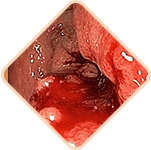

3 peligros mortales de hemorroides si no se trata a tiempo

Cualquiera de los siguientes puede ser

la causa de la muerte súbita del paciente!

Las heces contienen una cantidad gigantesca de gérmenes, bacterias y hongos. Si la infección ingresa al tejido pélvico y a los órganos vecinos, es posibleuna inflamación peligrosa y una infección de la sangre

Los vasos llenos del bulto hemorroidal son muy débiles. A menudo se rompen. El grado de pérdida de sangre en este caso puede ser tal que sea necesario transfusión de sangre

Se forman coágulos de sangre en los vasos. Estos coágulos de sangre pueden desprenderse y obstruir los vasos de los órganos internos, interrumpir la circulación sanguínea y causar un bloqueo en las arterias pulmonares.La probabilidad de muerte es alta.